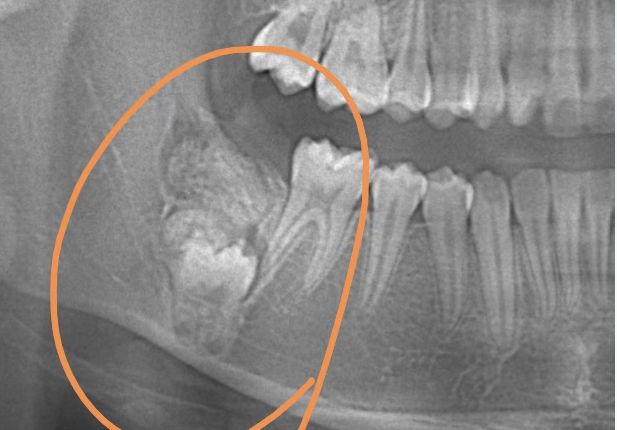

女童牙长不齐去矫正 竟照出牙齿下长肿瘤

中国上海市一名12岁女童因为牙齿长不齐,而到医院进行矫正治疗。医生拍X片时赫然发现,女童的右下颌骨内发生了瘤样病变,导致牙齿在长出来的途中遇到受阻,才无法正常长出。医院替她制定手术治疗方案,完全切除瘤体,已可正常进行后续的牙齿矫正。

《澎湃新闻》报导,由于女童的牙瘤就生长在颌骨内,手术难度较大,医疗团队使用了最新的超声骨刀微创去骨法,尽量保留正常的颌骨组织,最大程度保护黏膜组织及正常的恒牙。手术在全身麻醉下进行,医生在足够空间视野下操作,减少了手术时长,最大限度地减轻了患儿在心理和身体上的恐惧和疼痛。